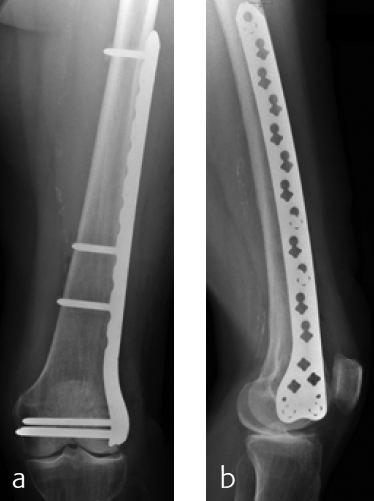

Case provided by Christoph Sommer, Chur, Switzerland

A 79-year-old woman fell downstairs at home and sustained a low-energy distal intraarticular femoral fracture. On conventional x-rays, the fracture seemed to be a unicondylar lateral split-type in rather osteoporotic bone (Fig 1). For detailed fracture analysis, a CT scan was performed that demonstrated a displaced lateral and nondisplaced medial condylar fracture (AO-33C1) (Fig 2). The fracture was very distal and therefore difficult to address with one lateral plate. Using VA technology in this situation provided the advantage of angulating the most distal anterior screw very close to the intercondylar notch in order to address the nondisplaced but fractured anteromedial condyle (Fig 3). Due to poor bone quality, a long plate was used to prevent a future periimplant fracture. Early follow-up showed uneventful healing with good function.